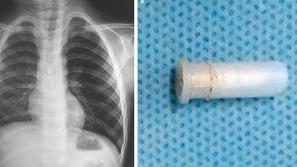

Deček pogoltnil piščalko in to je bilo slišati iz njegovih pljuč

Nenavadni primer "žvižgajočega kašlja."